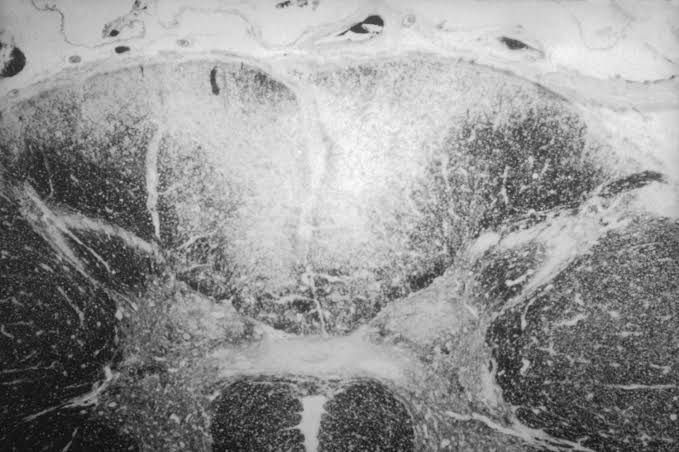

Tabes dorsalis is a slow degeneration of the nerve cells and nerve fibers that carry sensory information to the brain. The degenerating nerves are in the dorsal columns of the spinal cord (the portion closest to the back of the body) and carry information that help maintain a person's sense of position.